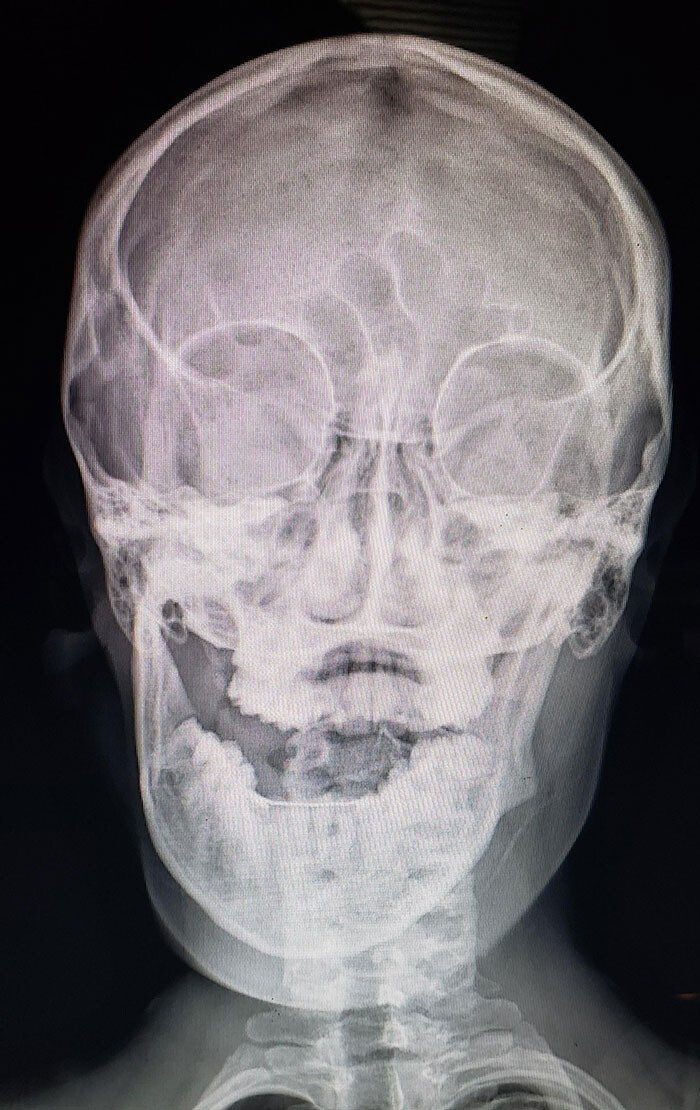

Рентген портрета Карла II Испанского показал, что он написан поверх первой версии, которую ходожник создал, когда король был несколькими годами младше